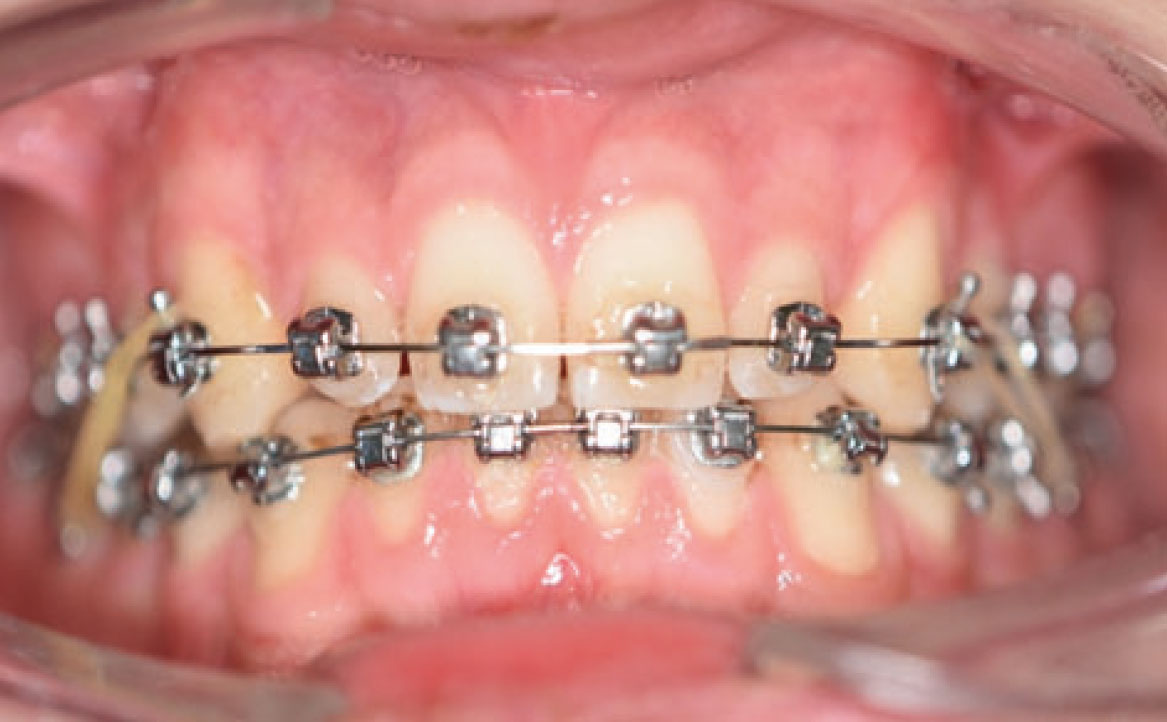

Dopo circa dieci mesi, è stata eseguita la rimozione dei rialzi occlusali ed è stato ridotto il tempo di utilizzo degli elastici da 24 a 12 ore (solo nelle ore pomeridiane e notturne) (fig. 6a-d). Successivamente, il paziente ha chiesto anche di migliorare l’aspetto estetico degli elementi microdontici 12 e 22. Dopo una discussione con un collega, è stata proposta l’aggiunta di materiali compositi sul lato mesiale e distale di entrambi gli elementi. L’alternativa sarebbe stata l’uso di faccette in composito.

Sei mesi dopo è stata eseguito il debonding di entrambe le arcate. Successivamente il paziente è stato sottoposto a una seduta di igiene orale professionale. Infine, sono state prese le impronte dentali per creare i retainers. Al termine del trattamento è ancora visibile uno spazio residuo compreso tra gli elementi 13-12 e 22-23 dopo l’intervento estetico con materiale composito. La classe molare è stata raggiunta (fig. 7a-e).